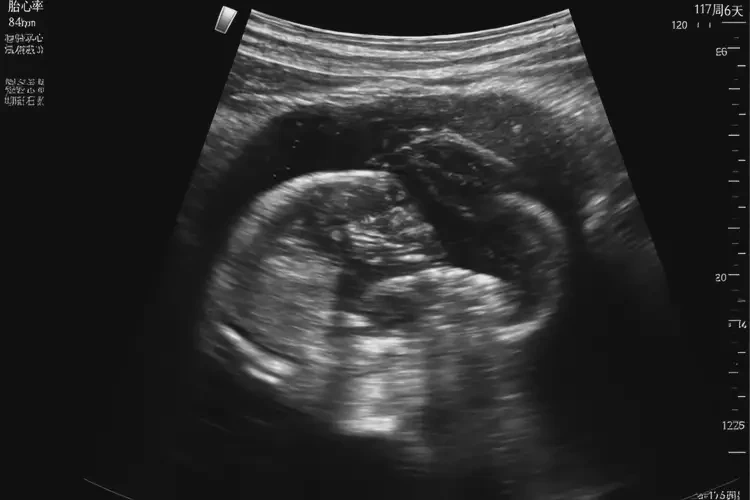

孕17周6天胎心84還要保胎嗎(圖1)

孕17周6天胎心84還要保胎嗎(圖2)

• 超聲檢查:通過使用超聲波來觀察胎兒的發(fā)育狀況和健康狀況。

孕17周6天胎心84還要保胎嗎(圖3) 孕17周6天胎心84還要保胎嗎(圖4)